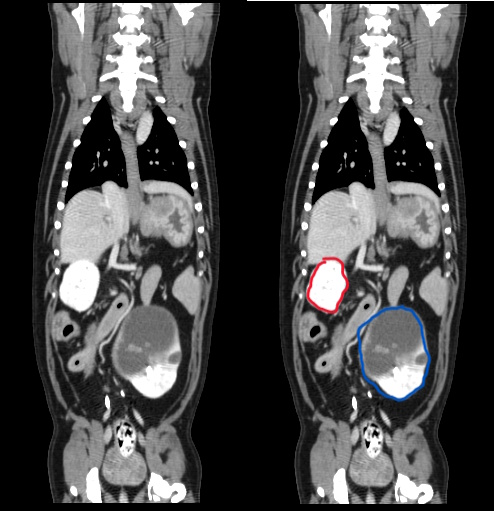

4) Cystic Kidney - incidental abdominal mass palpated during routine health exam

Blaze, 13 yr old chihuahua, was referred for surgery after his primary care veterinarian palpated an abdominal mass during a routine wellness exam. Abdominal radiographs were obtained, and a splenic mass was suspected.

We recommended additional diagnostics to identify the origin of the mass and to check for evidence of metastasis prior to an exploratory abdominal procedure.

Abdominal and thoracic studies pre and post contrast were obtained. Whilst the spleen appeared to be free of disease, the 3D renderings clearly showed a deformed left kidney. Review of the axial images showed a large abdominal mass originating from the left kidney. The right kidney appeared free from disease. No evidence of metastasis was detected within the chest or abdominal lymph nodes. The only abnormalities on lab work included mild elevations of ALT and BUN. Blaze was taken to surgery, where his left kidney was surgically removed. Histopathology confirmed the mass as a benign cystic structure.